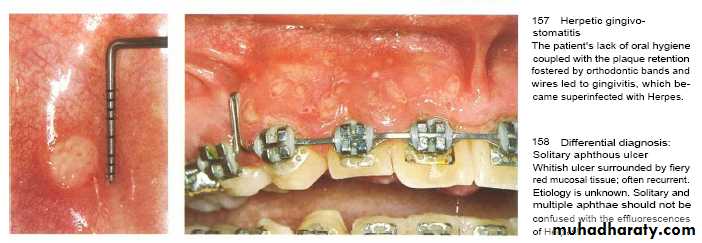

Viral infection

Herpes simplex virus type 1 & 2 & Varicella-zoster virus that inter body in childhood & induce lesion followed by period of recurrent infections occur in 20-40 % in form of herpes labialis.Factors triggering reactivation of latent virus are; Trauma , ultra violet light and fever .